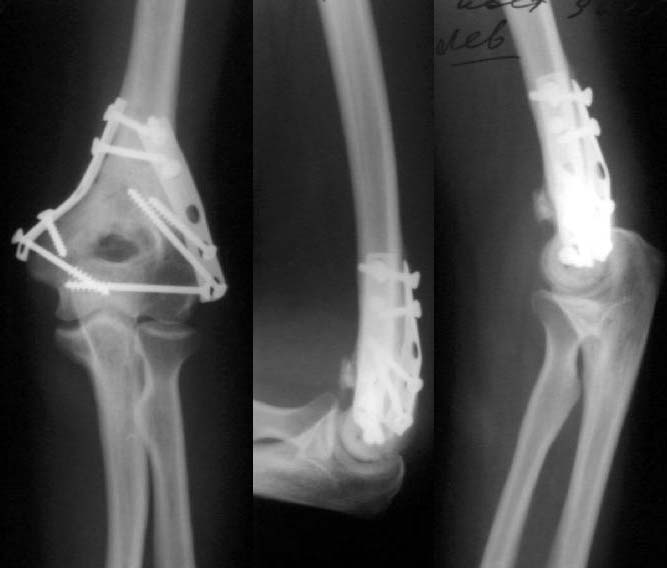

Женщина, 37 лет. Травма в результате падения на улице. Закрытый многооскольчатый перелом дистального метаэпифиза левой плечевой кости со смещением. Неврологических и сосудистых нарушений не выявлено.Лечение? Если внешняя фиксация, то - каков монтаж АВФ? Сейчас пациентка на скелетном вытяжении.С уважением,А.В.Владзимирский

До лечения

Результат в 6 месяцев

Лечение тут, видимо, должно основываться в первую очередь на открытой репозиции, поскольку возможности закрытой при таких повреждениях далеко недостаточны. Если поверхность блока состоит не просто из двух крупных фрагментов, лучше идти с отсечением локтевого отростка. Вопрос о методе фиксации более второстепенный. Можно и аппаратом. В приложении - пример лечения такого повреждения с внутренней фиксацией.

Все же открываться мы не стали. Результаты в приложении. Фронтальный снимок переделаю и пришлю еще раз. Мнения?